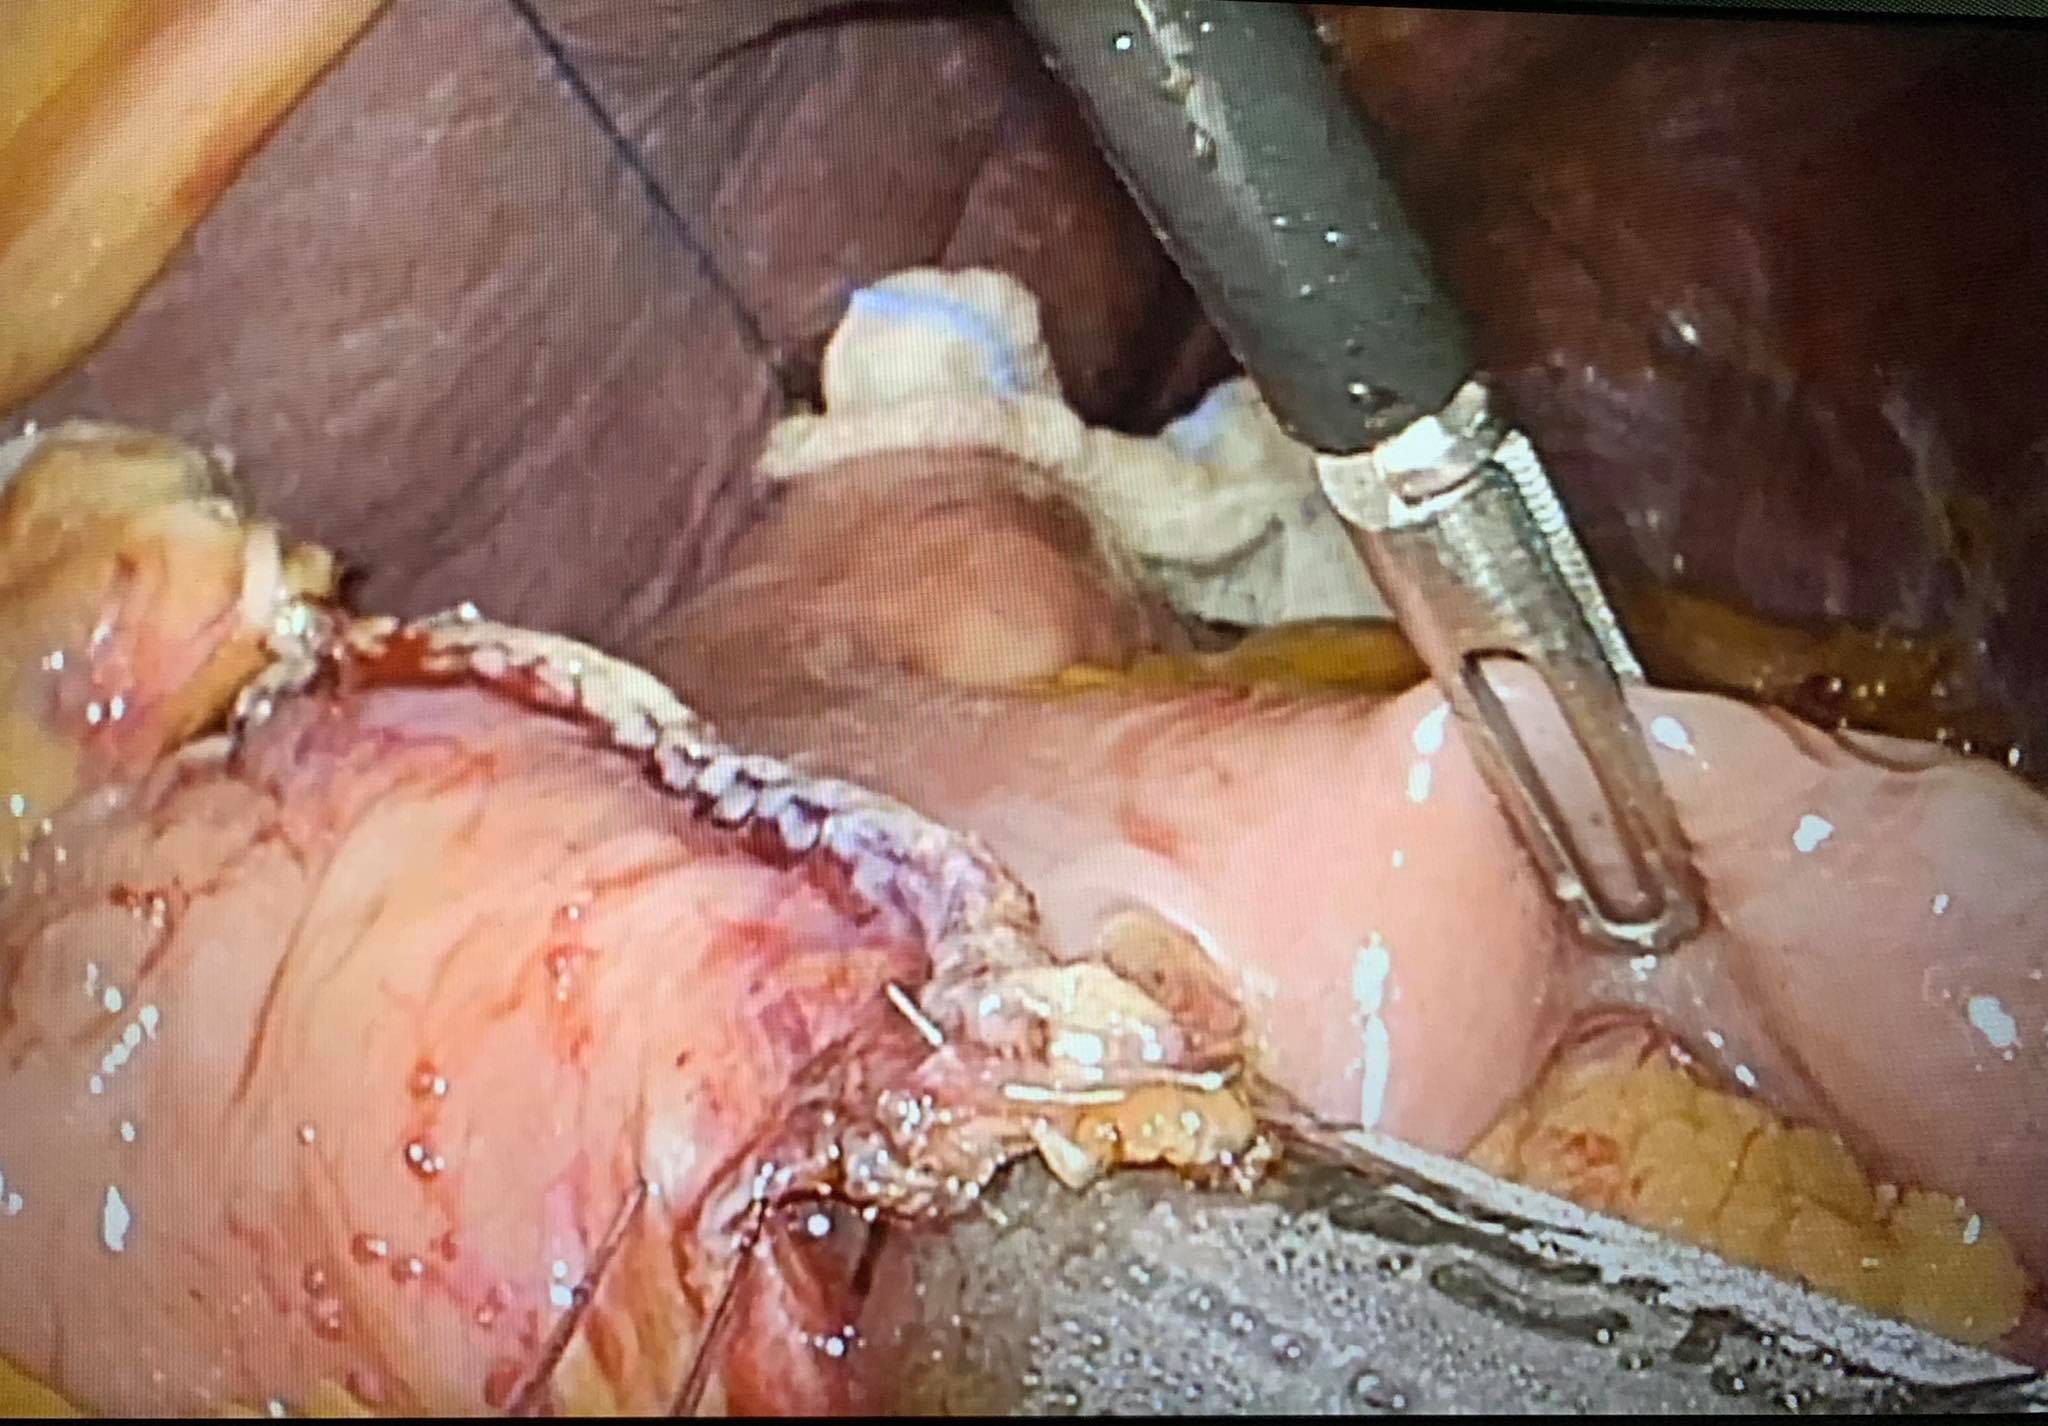

Hình 4: Miệng nối hỗng tràng-phần xa dạ dày.